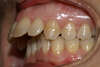

Vues avant le traitement